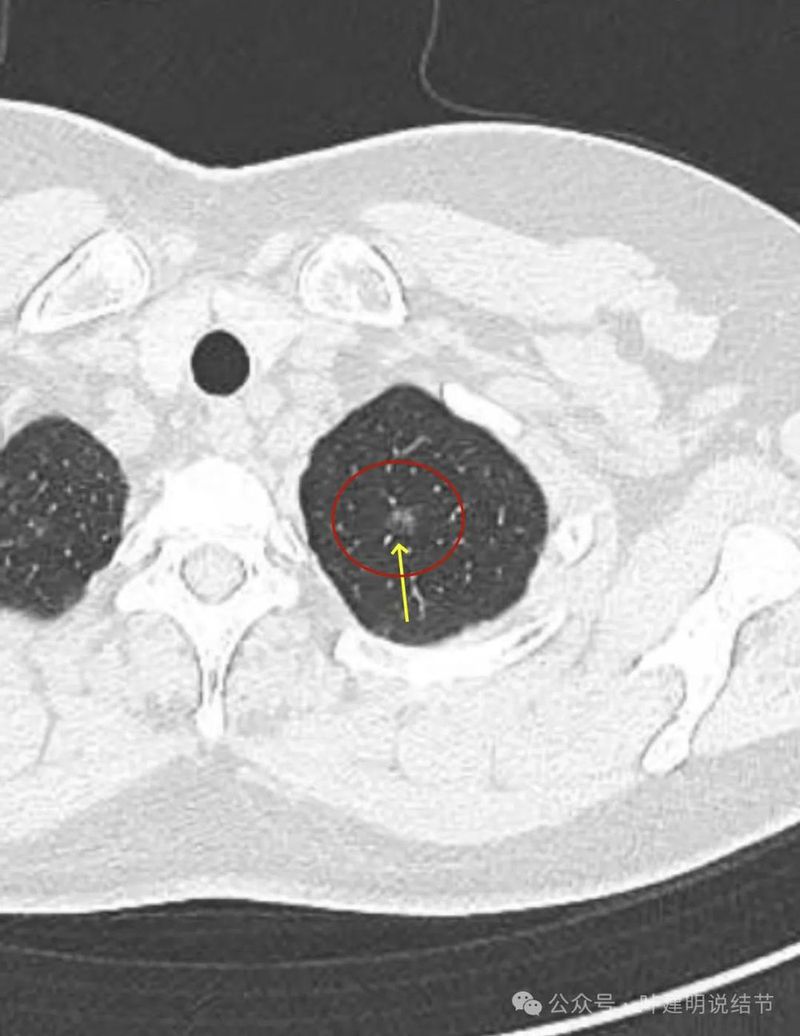

灶内见到血管穿行,整体轮廓清楚,密度欠均。

有明显磨玻璃成分,有血管紧贴,有小血管穿行,整体轮廓与边界清。

整体密度较高,有血管贴着,边缘少许磨玻璃成分。